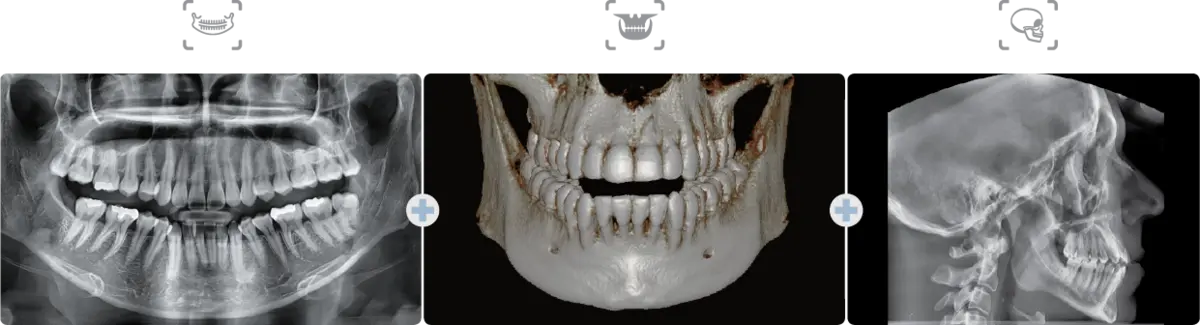

CBCT, 파노라마 등 디지털 영상장비는 치과 진료의 핵심 인프라입니다. 장비에 장애가 발생하면 영상 촬영이 불가능해지고, 그날의 임플란트 수술과 교정 상담이 모두 지연됩니다. 백덴탈은 Vatech 공식 서비스 파트너로서 장비의 안정적 운용을 책임집니다.

EzDent-i, Ez3D-i 등 Vatech 영상 소프트웨어의 최신 버전을 설치하고, 기존 환자 데이터와의 호환성을 확인합니다. 새로운 기능 추가, 보안 패치, 성능 개선 사항을 적용하여 항상 최적의 소프트웨어 환경을 유지합니다.